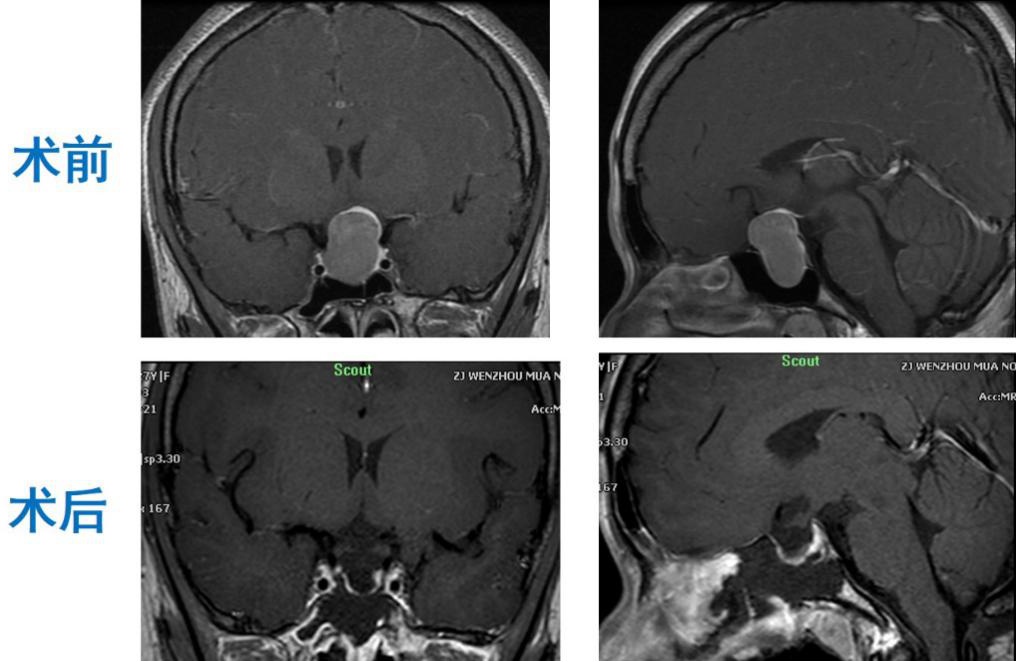

复查结果显示,她的垂体激素均恢复到正常水平,磁共振检查提示肿瘤完全切除。

▲ 磁共振检查提示肿瘤完全切除